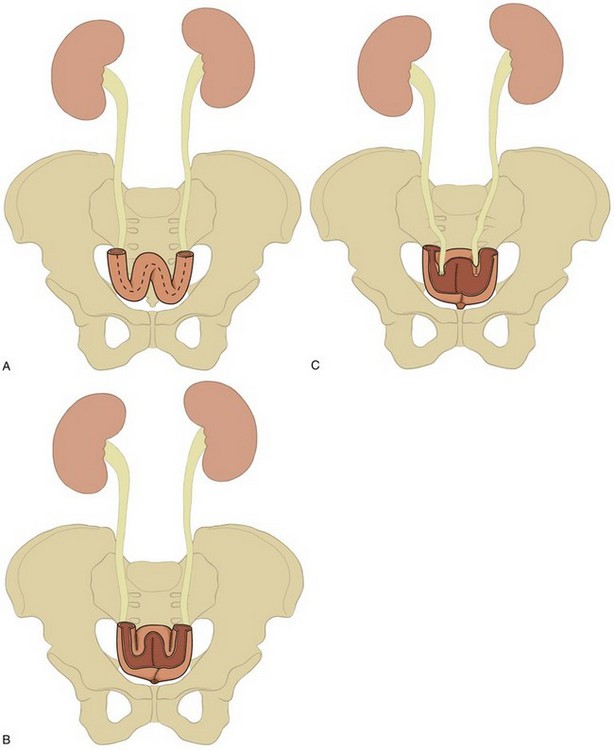

The colon receives its blood supply from the superior mesenteric artery, inferior mesenteric artery, and internal iliac arteries (Fig. 85–2). The major arteries supplying the colon and rectum include the ileocolic, right colic, middle colic, left colic, sigmoid, superior hemorrhoidal, middle hemorrhoidal, and inferior hemorrhoidal arteries. These arteries anastomose one with the other to form the arc of Drummond and allow considerable leeway in mobilizing the colon. The middle colic artery arises from the first portion of the superior mesenteric artery and generally ascends the transverse mesocolon to the right of midline. The right colic artery usually arises just below the middle colic artery from the superior mesenteric artery and courses to the right colon. It may arise, however, from the ileocolic artery or directly from the middle colic artery. If it arises from the ileocolic artery, mobilization of the distal ascending colon is facilitated so that this portion of the colon can easily be brought into the deep pelvis. On occasion, however, it is necessary to sever the right colic artery at its origin to mobilize the distal portion of the ascending colon to the pelvis. This is particularly true if the right colic artery originates from the middle colic artery. The ileocolic artery is the terminal portion of the superior mesenteric artery and supplies the last 6 inches of ileum and ascending colon. The left colic artery arises from the inferior mesenteric artery, and then the inferior mesenteric artery gives off four to six sigmoid branches, the last of which becomes the superior hemorrhoidal artery. This anastomoses with the middle hemorrhoidal artery, a branch of the internal iliac artery, which in turn anastomoses with the inferior hemorrhoidal artery, the terminal branch of the internal pudendal artery. The middle sacral artery, which originates directly from the aorta, may supply the posterior aspect of the rectum.

The incidence of intestinal obstruction after abdominal procedures for urinary intestinal diversion differs according to whether the stomach, ileum, or colon is used for the diversion. In patients who have had a segment of stomach or ileum removed for the diversion, there is a 10% incidence of postoperative bowel obstruction requiring treatment. When the colon is used, the incidence of postoperative obstruction requiring an operation is 5% (Table 85–3). Half of the bowel obstructions occur in the early postoperative period. In one series, after radical cystectomy and ileal conduit, 15% of the patients had a mild obstruction in the first 6 months that responded to conservative management, whereas 3% required an operation to relieve the obstruction during this period. The occurrence of obstruction after this 6-month period was much less frequent (Sullivan et al, 1980). More recently, a 10.5% incidence of reoperation for bowel obstruction was noted in a large series of radical cystectomy patients (Varkarakis, 2006). Bowel obstruction can be a morbid event: A significant number of patients who develop obstruction after an ileal conduit and require an operation die. The most common cause of the obstruction is adhesions, followed by recurrent cancer. These two causes account for the great majority of the cases. Volvulus and internal hernia account for far fewer cases (Jaffe et al, 1968). Rarely, severe stenosis or obstruction at the anastomotic suture line occurs. Stenosis is a result of edema, poor technique, or performing the anastomosis on ischemic bowel (Fig. 85–16); obstruction is a result of improper technique.

The incidence of postoperative bowel obstruction may be reduced by using nonirradiated bowel, performing the anastomosis on well-vascularized bowel, closing all apertures, reperitonealizing the isolated segment, decompressing the gastrointestinal tract for an adequate time, placing omentum over the anastomosis, and reconstituting the pelvic floor after exenterative surgery. The isolated segment is reperitonealized by tacking its antimesenteric border to the lateral abdominal sidewall peritoneum. The proximal mesenteric border should be tacked to the posterior parietal peritoneum because failure to obliterate this potential space has resulted in entrapment of bowel, causing a bowel obstruction. Placing the sigmoid colon in the area may close the pelvic space left after an anterior exenteration. This effectively prevents small bowel from herniating into the raw pelvis. Omentum may also be mobilized and used to fill any space the sigmoid colon does not fill. In a total exenteration, sufficient sigmoid colon is not available and the omentum is often not bulky enough to fill the pelvis and thus prevent small bowel from filling the denuded pelvis. This situation is of particular concern in patients who must receive postoperative pelvic irradiation. The bowel may be kept out of the pelvis in these patients by reconstructing the pelvic floor with polyglactin mesh. The mesh is sutured along the posterior pelvic brim to the sacral promontory and presacral fascia and laterally to the adventitia of the iliac vessels. Laterally and anteriorly, it is sewn to the peritoneum two thirds of the distance between the pubis and umbilicus. Omentum is then brought down, placed over the mesh, and sutured in position. This effectively excludes the bowel from the pelvis for 4 to 6 weeks while postoperative irradiation is being administered (Sener et al, 1989).